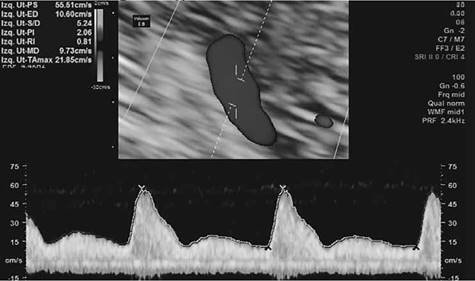

Llama la atención en la evaluación del doppler de arterias uterinas un IP alterado con valor medio de 2.06. Figura 3.

En la correlación del oligohidramnios severo más el Doppler de arterias uterinas alterado y descartando etiologías como ruptura prematura de membranas, infecciosas, enfermedades autoinmunes y trombofilias se concluye diagnóstico de insuficiencia placentaria y se inicia tratamiento con enoxaparina 40 UI por vía subcutánea como terapia profiláctica para mejorar circulación útero - placentaria.